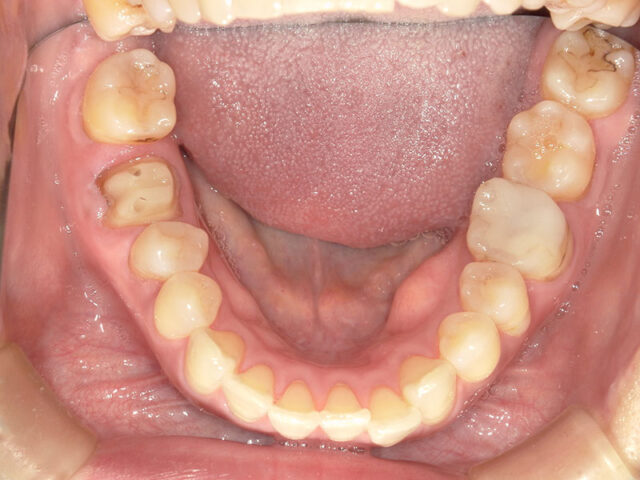

Before

After

| 通院回数 | 12回(治療期間1年) |

|---|---|

| 通院目的 | 歯の移植の相談をしたい |

| 処置内容 | 歯牙移植 |

| 費用 | 移植 15万 根管治療 6万 コア 1万 セレッククラウン 7万 |

| デメリット・注意点 | 生着を必ずするとは限らない 外部吸収のリスクがある 咬合時の違和感が生じる場合がある 失敗した場合には、インプラントを行うに際して骨造成を必要とする。 インプラント治療に比べ、予後が不明確 |